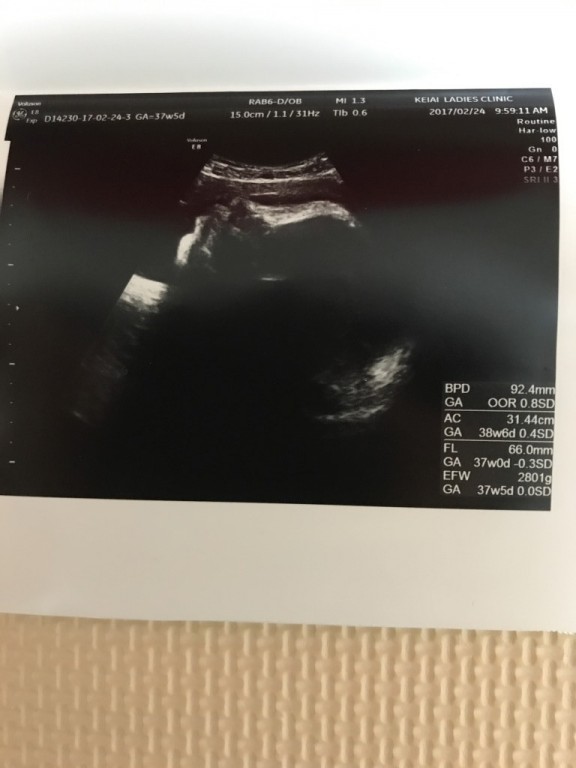

- 妊娠10ヶ月 37週0日 撮影日:2018年02月24日